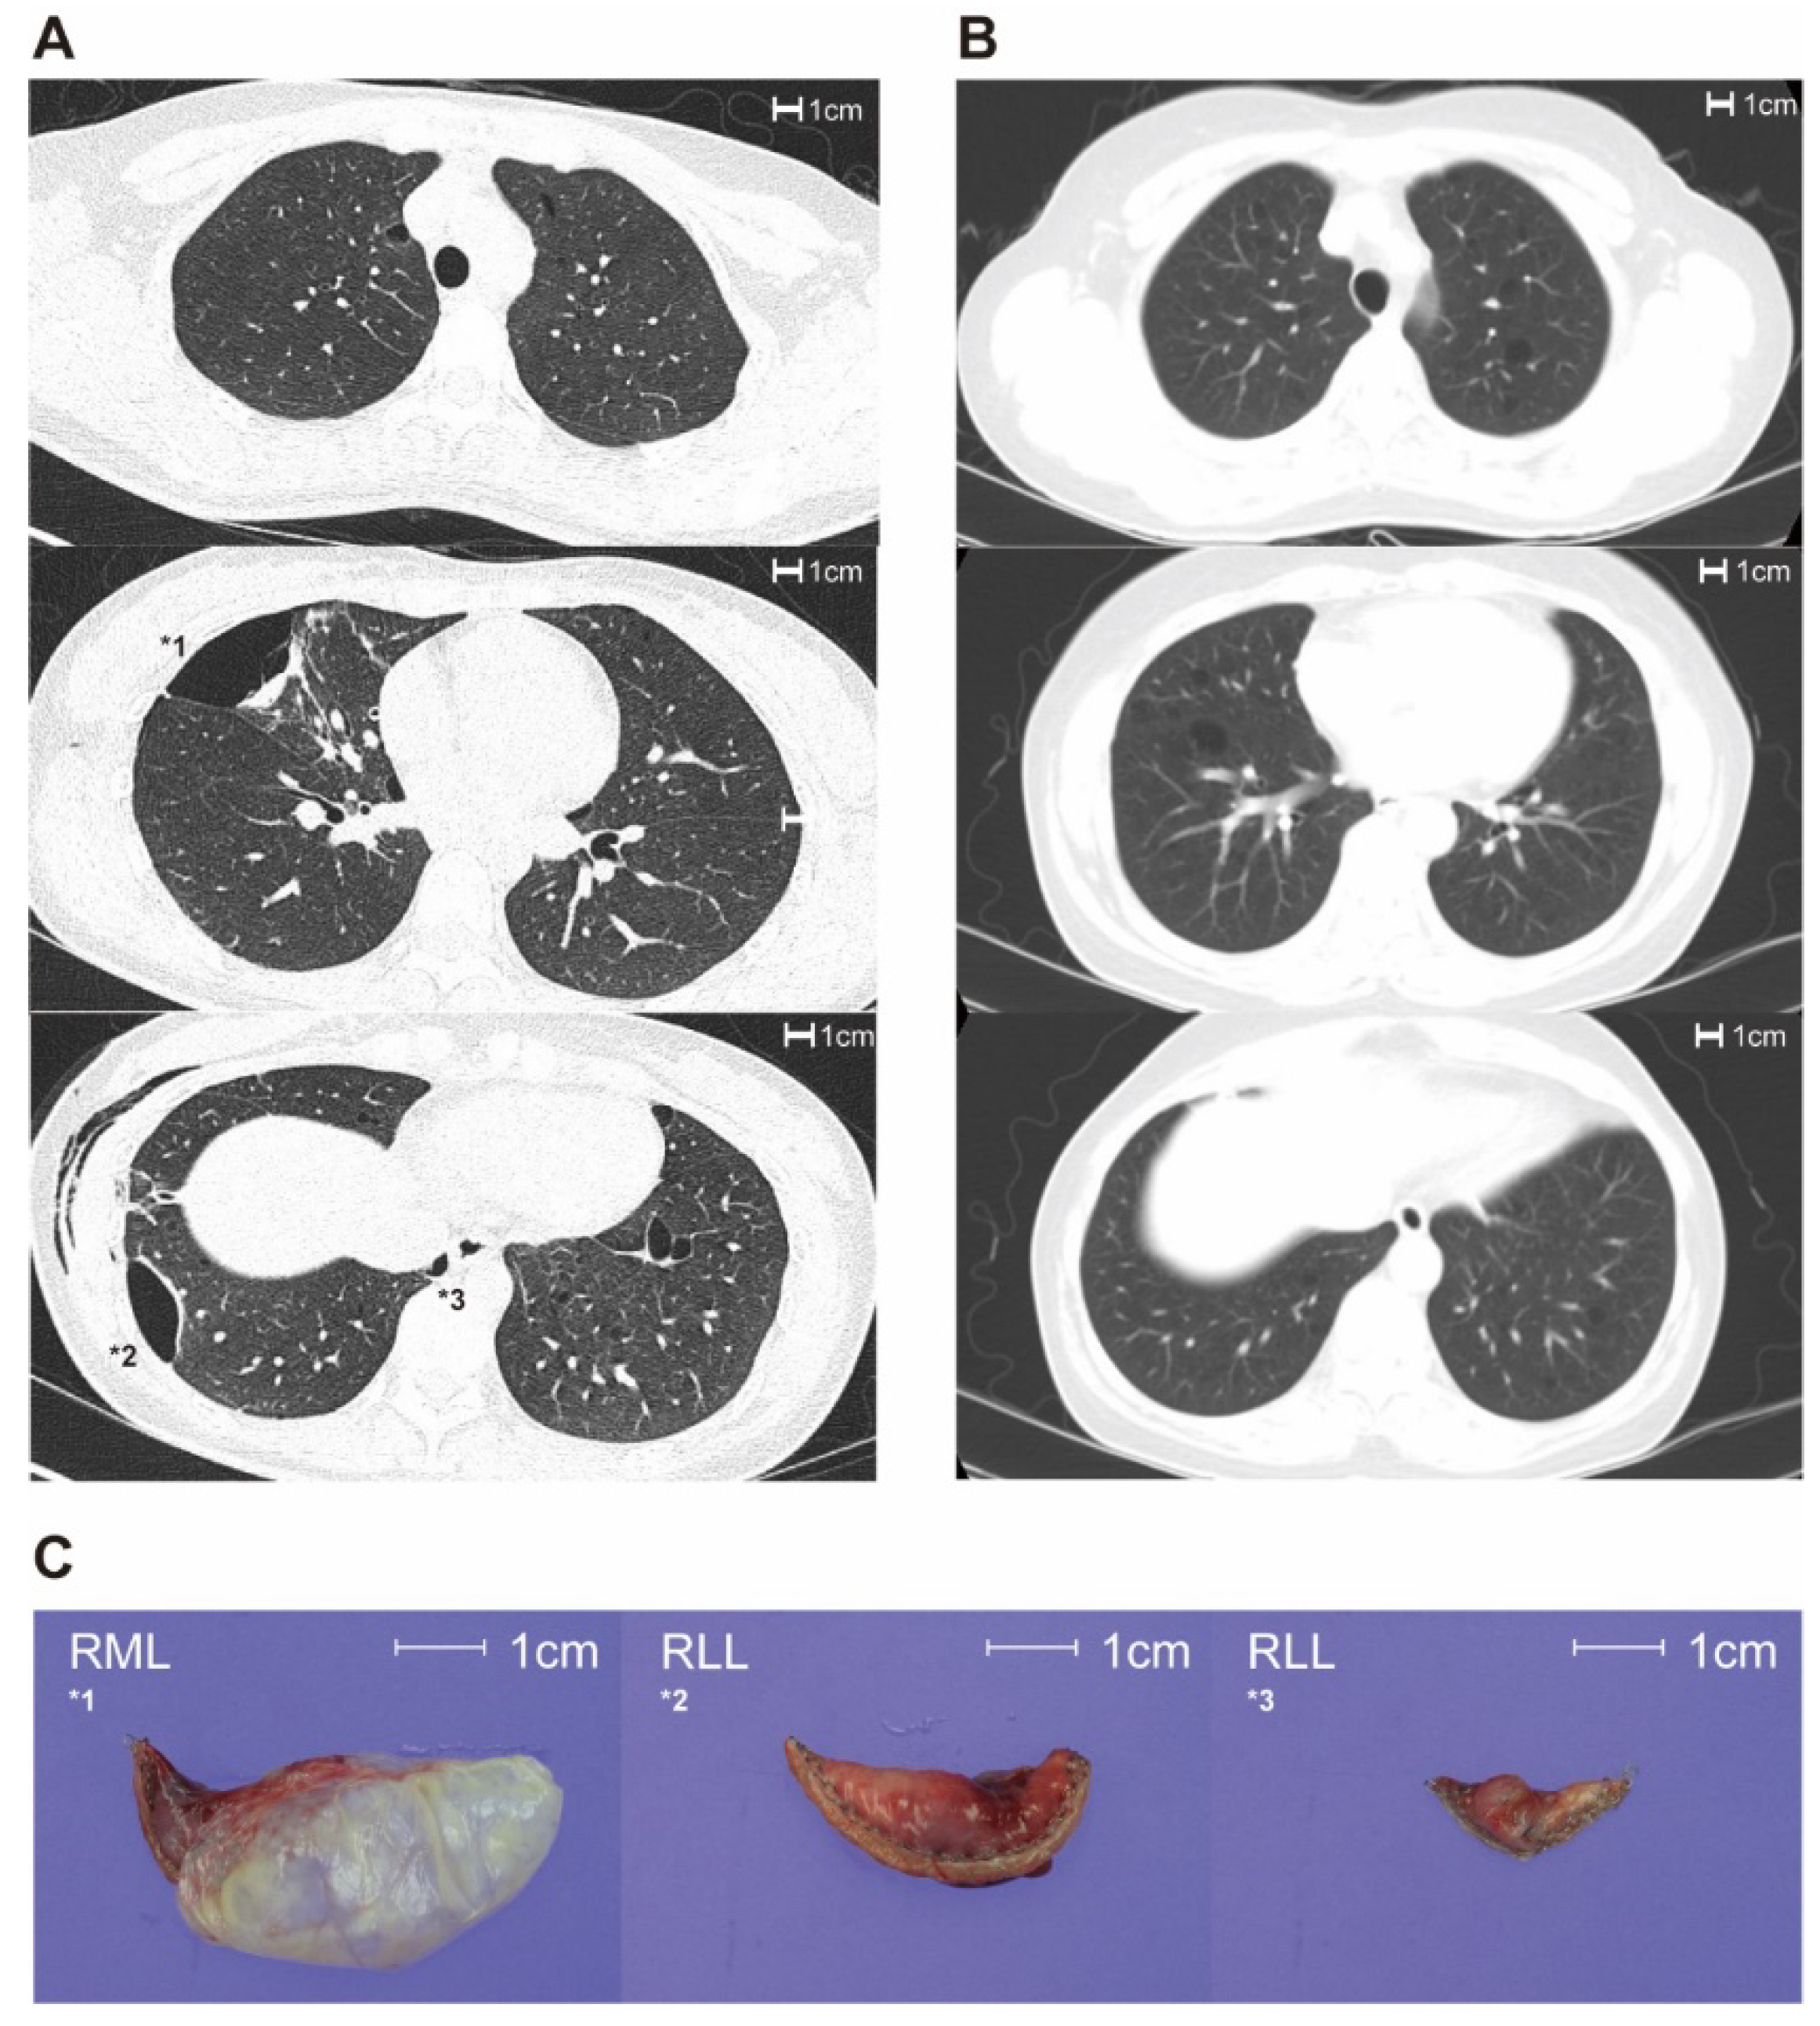

Lung cysts on chest CT exhibited different characteristics in patients with and without BHD (Figure 1). Over 80.0% and 72.7% of patients in the BHD and non-BHD groups exhibited >40 lung cysts, respectively, without significant differences between the groups (p = 1.000; Table 3). The maximal diameter of the lung cysts was significantly greater in the BHD group than in the non-BHD group (4.1 ± 1.1 cm vs. 1.6 ± 0.9 cm, p < 0.001). Lung cysts were diverse in size and morphology in all BHD cases, and diversity was more prevalent in the BHD group than in the non-BHD group (100% vs. 18.2 %, p = 0.001 and 100% vs. 54.5%, p = 0.054, respectively).

Figure 1. Differences in the characteristics of lung cysts between the BHD and non-BHD groups. (A): Transverse plane view of chest computed tomography for BHD patients. (B): Transverse plane view of chest computed tomography for non-BHD. (C): Gross pathology images of lung cysts in BHD patient, The number of cyst is same as marked number in chest computed tomography image (A). BHD: Birt–Hogg–Dube syndrome.